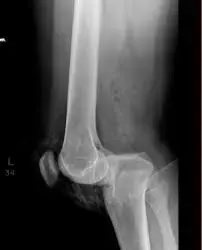

الأشعة السينية (X-rays):

ضرورية للكشف عن كسور العظام، وجود شظايا أسنان متبقية داخل الجرح (الأسنان تظهر بوضوح في الأشعة)، أو وجود غاز في الأنسجة الرخوة أو داخل المفصل (مؤشر لعدوى بكتيرية منتجة للغاز).

| وجود كسور أو شظايا أسنان | يمكن الكشف عنها بالأشعة السينية، وتزيد من تعقيد الإصابة وخطر العدوى وتتطلب إزالة الشظايا وتنظيف الكسر. |